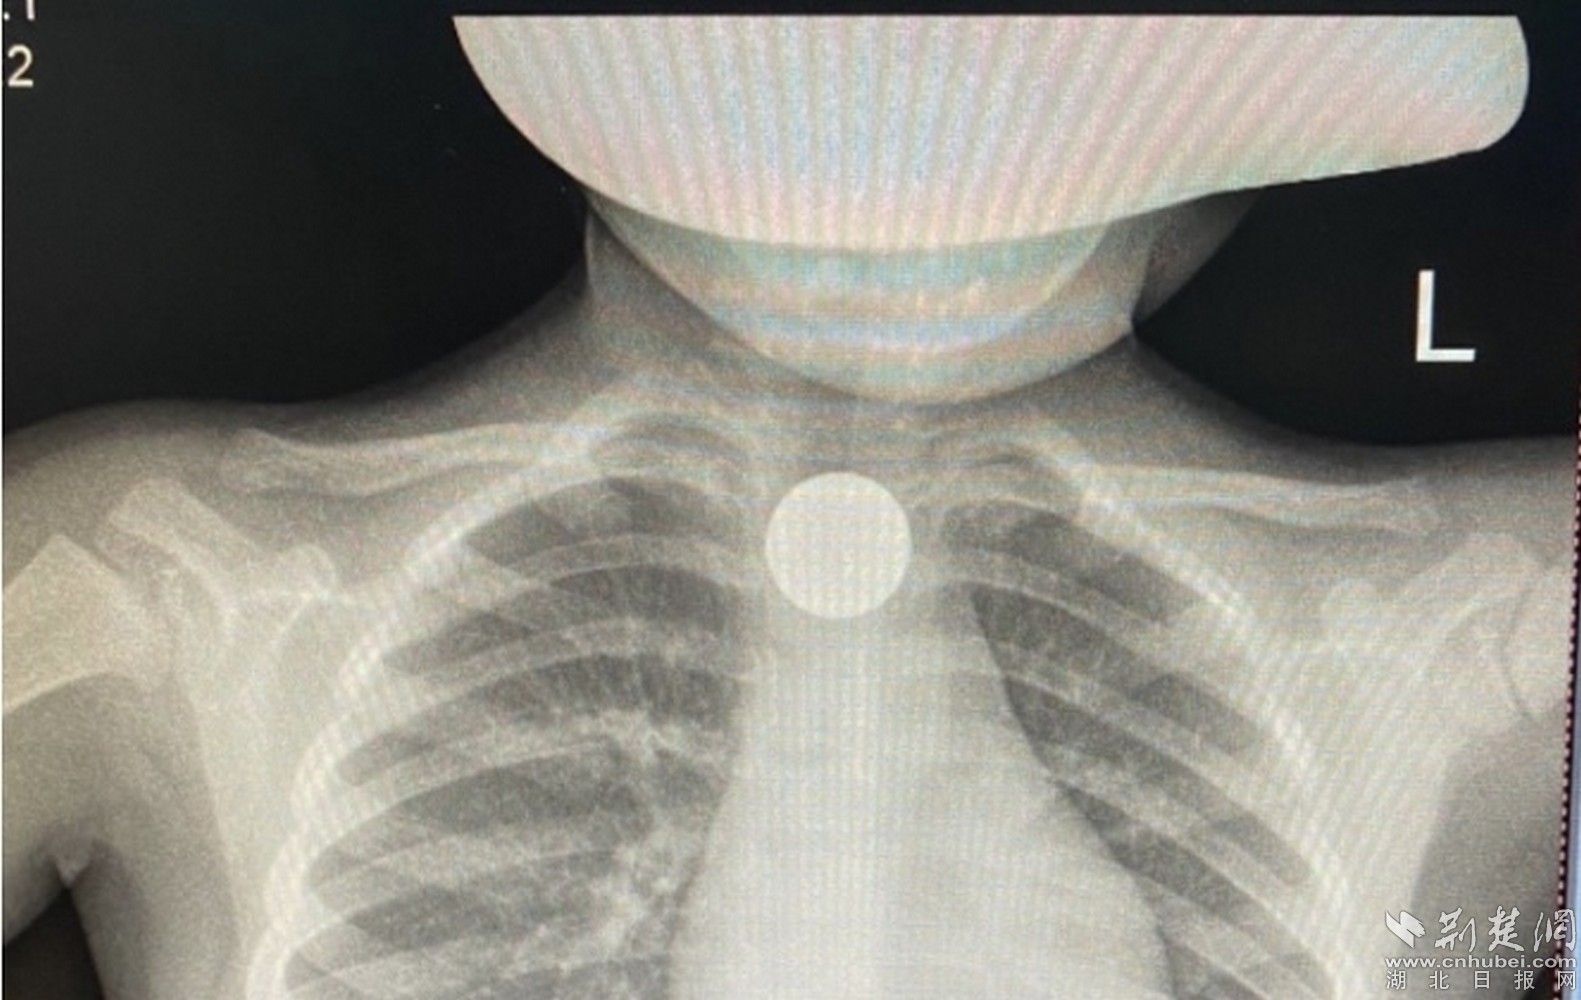

据患儿家长介绍,孩子玩耍时,不慎将一枚硬币吞食。因硬币卡住喉咙,孩子一直咳嗽,家长了解情况后立即带患儿来到孝感市中心医院消化内科就诊。经胸部CT检查,发现食管胸段见直径约2.4cm类圆形异物,若不及时取出,容易造成食道穿孔、破裂,继发感染,情况严重可危及生命。

消化内科副主任钟碧波借助胃镜,在护士的配合下,用圈套器夹紧硬币,仅用五分钟就把硬币取出,并通过胃镜观察患儿食管壁,发现没有损伤、没有出血,患儿没有出现身体不适。